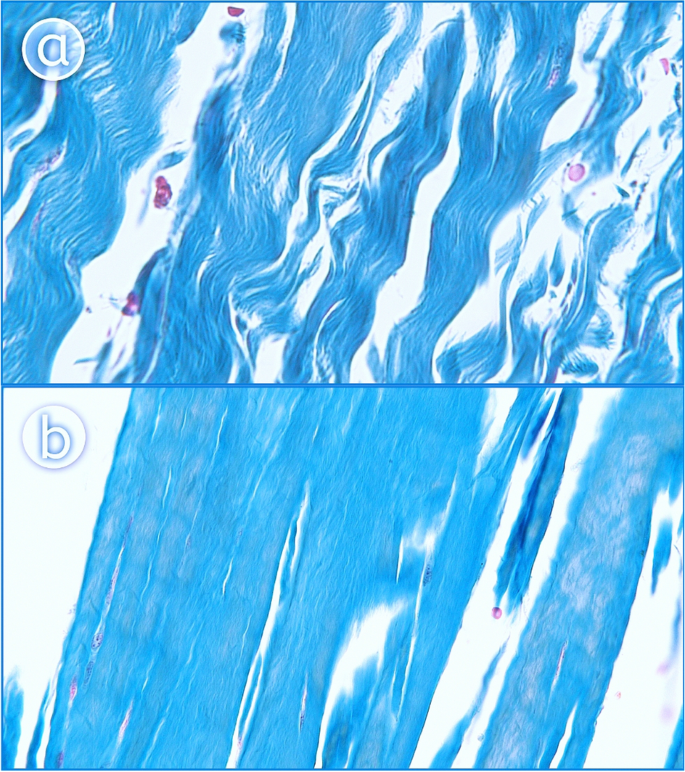

Histological study

After the PPM and popliteo-fibular ligament was collected, specimen were fixed in buffer (10% aqueous formalin) and then embedded in paraffin wax blocks. 8–10 µm thick histological slices were cut with a microtome (Semiautomatic microtom SLEE CUT5062, OPTA-TECH, made in Germany) and stained with hematoxylin and eosin and by Azan’s method to highlight the basic features of tissue architecture. Stained PPM and PFL slices were photographed using an Olympus CX43 (Olympus Corporation Japan) light microscope and an Olympus EP50 camera (Olympus Corporation Japan). Pictures were taken 2 × and 400 × and 600 × magnifications.

The PFL was not considered in the classification due to being a ligamentous structure (Fig. 5a). The other bands (to the posterior capsule, to the fibular collateral ligament, to the lateral meniscus, to the meniscofemoral ligament) had tendinous texture in histological examination (Fig. 5b).

Histological examination of the accessory bands of the popliteus muscle. A 400 magnification—ligament. B 400 × magnification—tendon. The Fig. 5 was taken with Olympus EP50 camera (Olympus Corporation Japan), and the signatures were made in Corel DRAW 12 (https://www.coreldraw.com/pl/pages/coreldraw-12/).